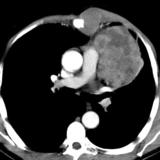

Case 8c Thymoma CT

Date: 03/27/2009

Views: 15480